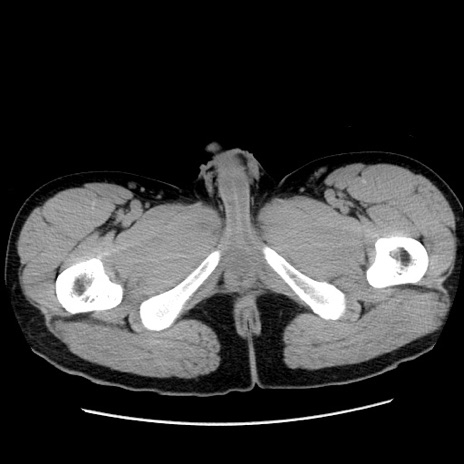

症例36(横断像)

【症例】20歳代 男性

【主訴】心窩部痛

【現病歴】今朝より上腹部痛あり。一旦軽快していたが再度出現したため救急要請。昨日夕に白身の魚を含む刺身を食べた。

【身体所見】BP 136/89mmHg、HR 74/min、BT 37.0℃、腹部:膨満、軟、心窩部に圧痛あり。反跳痛なし、筋性防御なし、腸雑音やや亢進あり。

【データ】WBC 17700、CRP 0.48